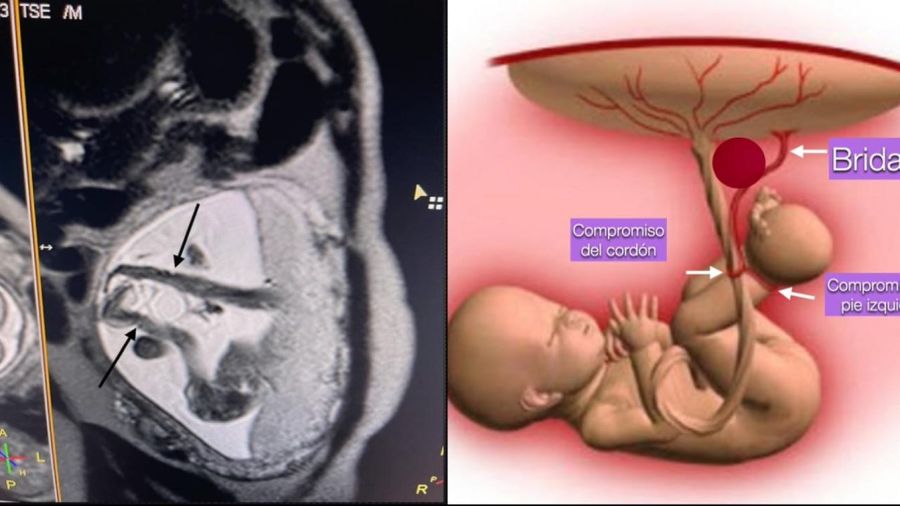

“Las bridas amnióticas es una condición rara, que se da cuando se forman “fibras” o “bandas” en el saco amniótico durante el período embrionario. Estas bandas pueden terminar envolviendo una extremidad u otra estructura fetal, como el cordón umbilical. Esto puede causar complicaciones graves e, incluso, la muerte del feto, en los casos en donde el cordón umbilical se estrangula”, le explicó a PERFIL el cirujano Daniel Russo, director del Programa de Cirugía Fetal del Hospital Universitario Austral y responsable de la puesta a punto de esta nueva opción quirúrgica que puede salvar al bebé.

En concreto, hasta ahora el equipo de cirugía fetal del Hospital Austral, integrado por seis personas, usó este procedimiento para prevenir problemas en dos embarazos. En uno, en un feto de apenas 19 semanas y en otro de 22 semanas. Por lo tanto, ninguno de los dos era viable si la operación salía mal. Sin embargo, los profesionales evaluaron -junto a la familia— que el riesgo de vida para estos fetos era muy alto si no se hacía la intervención. En ambos casos estaba involucrado el cordón. Y ambos bebés nacieron sanos.

Entre los estudios diagnósticos puede incluirse una ecografía que puede dar señales de hinchazón o edema de un miembro afectado o que dejó de crecer al ritmo esperado para esa etapa del desarrollo. También puede indicarse una resonancia magnética que ayuda al equipo médico a valorar la gravedad de la constricción que puede estar causando la brida y las eventuales anomalías asociadas, y un ecocardiograma fetal que sirve para examinar la estructura y la función cardíaca del bebé.